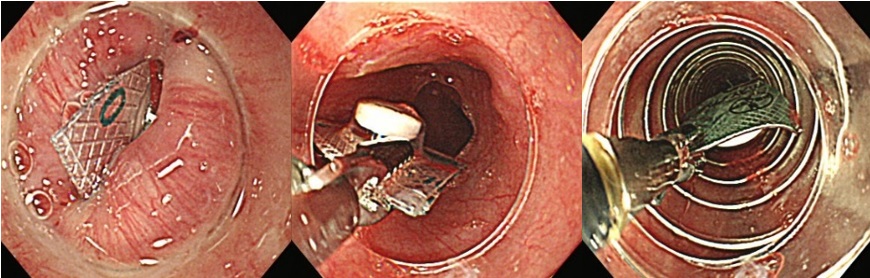

大腸ポリープ切除術、早期癌に対する内視鏡的粘膜剥離術、胃潰瘍などからの出血に対する内視鏡的止血術、食道静脈瘤からの出血に対する結紮術、アニサキス(寄生虫)や薬パッケージの誤飲に対する異物摘出術など。また胆道・膵臓系では、内視鏡を用いた胆石除去や、胆道感染や癌に伴う黄疸に対する内視鏡的な減黄術(ステント留置術)など各種行っております。

『薬パッケージの誤飲に対する異物除去術』